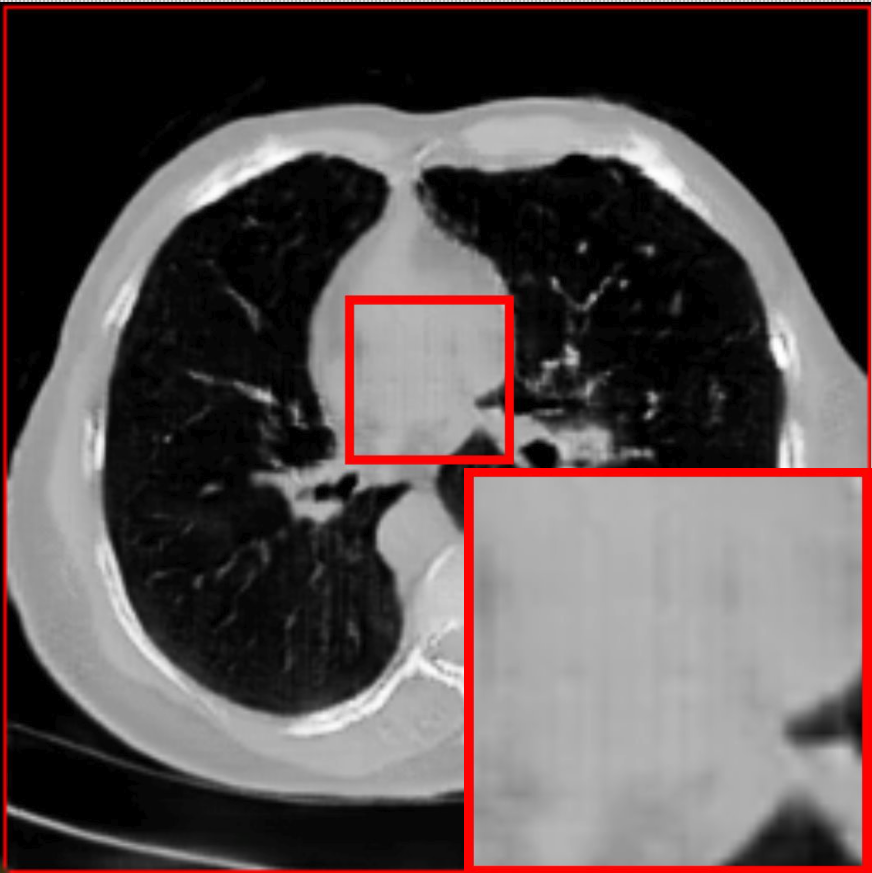

HA-GAN (sun2022hierarchical)

GenerateCT (hamamci2024generatect)

MedSyn (xu2024medsyn)

MAISI-DDPM (guo2025maisi)

MAISI-v2

Figure 2: Qualitative comparison across axial (top row), sagittal (middle row), and coronal (bottom row) views. Columns correspond to different methods. MAISI-DDPM and MAISI-v2 in this figure are unconditional synthesis which do not use ControlNet or segmentation maps.

Qualitative Evaluation:

Figure 2 presents representative slices from the axial, sagittal, and coronal planes. GenerateCT (hamamci2024generatect) is a 2D model, so it lacks inter-slice consistency, leading to poor image quality in the sagittal and coronal views. MedSyn (xu2024medsyn) produces noticeably blurry results with mosaic-like artifacts, such as region inside the red box. HA-GAN (sun2022hierarchical) generates visually sharp images but with mosaic-like artifacts, such as region inside the red box. Also, its voxel spacing is not available, which limits its applicability in real-world medical imaging tasks. Moreover, all three methods are restricted to synthesizing small anatomical regions. In contrast, both MAISI and MAISI-v2 are capable of generating high-quality 3D volumes that span larger body regions while preserving fine anatomical details and realistic structure.